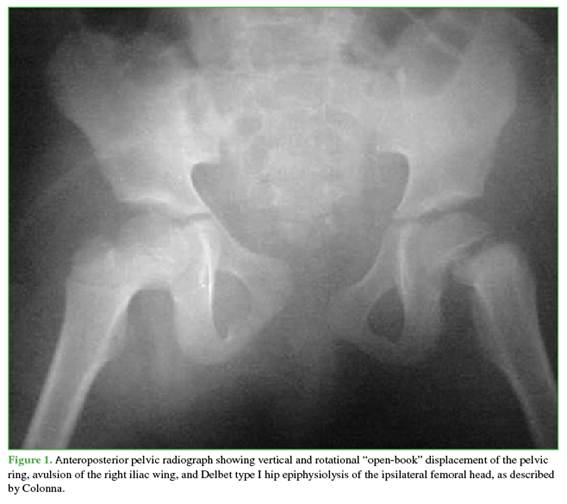

Of all the radiographs obtained, the AP pelvic radiograph revealed fractures consistent with polytrauma (Figure 1). A type C pelvic fracture according to the AO classification was observed, along with an avulsion of the iliac wing and a type A fracture within the same classification.1 In the left proximal femoral epiphysis, a type I (transepiphyseal) epiphysiolysis was identified according to the Delbet classification (Figures 2 and 3). 2